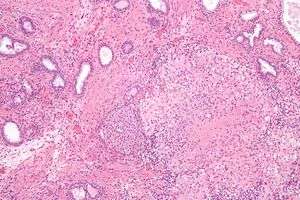

![]() Microscopic image of the Calmette-Guérin bacillus, Ziehl–Neelsen stain, magnification:1,000nn | |